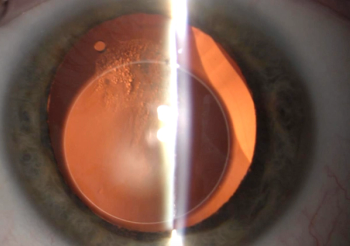

Prof. Peter Szurman, Head of Department, Eye Clinic Sulzbach, Knappschaftsklinikum Saar, Germany speaks about the DMEK (re)evolution in corneal transplantation surgery and the future of GEUDER's DMEK cartridge for transportation and injection of pre-loaded and pre-cut Descemet lamellas.